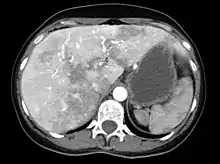

CT-scan of vascular malformations in the liver in a patient with hereditary hemorrhagic telangiectasia causing an inhomogeneous perfusion pattern.

Liver AVMs may be suspected because of abnormal liver function tests in the blood, because the symptoms of heart failure develop, or because of jaundice or other symptoms of liver dysfunction. The most reliable initial screening test is Doppler ultrasonography of the liver; this has a very high sensitivity for identifying vascular lesions in the liver. If necessary, contrast-enhanced CT may be used to further characterize AVMs.[1][2][6] It is extremely common to find incidental nodules on liver scans, most commonly due to focal nodular hyperplasia (FNH), as these are a hundredfold times more common in HHT compared to the general population. FNH is regarded as harmless. Generally, tumor markers and additional imaging modalities are used to differentiate between FNH and malignant tumors of the liver. Liver biopsy is discouraged in people with HHT as the risk of hemorrhage from liver AVMs may be significant.[6][7] Liver scans may be useful if someone is suspected of HHT, but does not meet the criteria (see below) unless liver lesions can be demonstrated.[7]